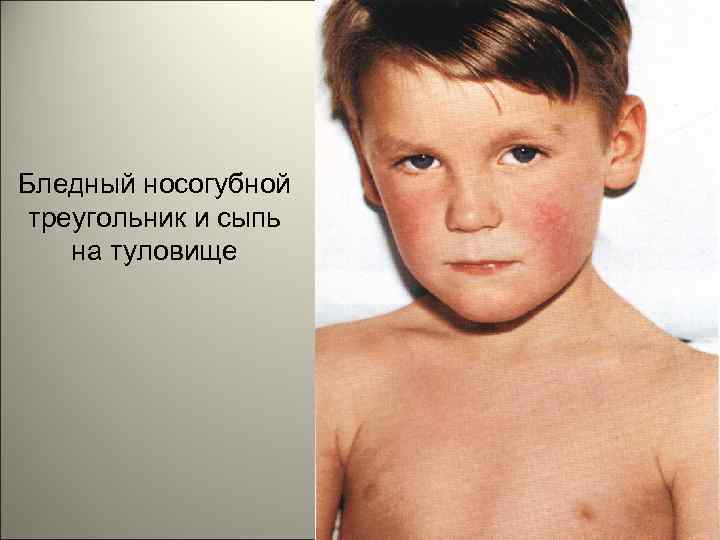

• К концу первых и на вторые сутки появляется характерная экзантема. На фоне гиперемированной кожи возникает яркая мелкоточечная сыпь, которая сгущается в области естественных складок кожи (подмышечные впадины, паховые складки, внутренняя поверхность бедер). 141

• На лице отмечаются яркая гиперемия щек и бледный носогубной треугольник. По краям румянца можно различить отдельные мелкоточечные элементы сыпи. В складках кожи (особенно в локтевых сгибах) отмечаются мелкие кровоизлияния, которые, сливаясь, образуют своеобразную насыщенную окраску складок (симптом Пастиа). 142

Бледный носогубной треугольник и сыпь на туловище 143